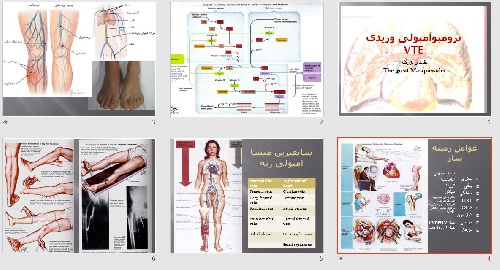

قیمت: 32٬000 تومان - دسته بندی فایل: عمومیترومبو آمبولی وریدی(VTE) (ppt) 20 اسلاید

پاورپوینت با عنوان ترومبوآمبولی وریدی - در فرمت پاورپوینت . 20 اسلاید قابل ویرایش